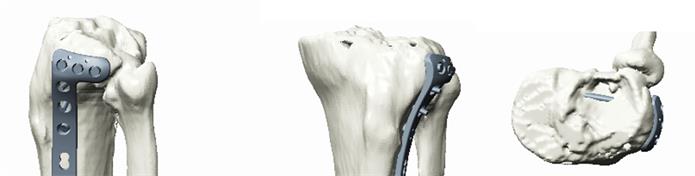

- 3D打印的骨折模型實(shí)物,供醫(yī)生進(jìn)行手術(shù)模擬、內(nèi)植物選擇、提前預(yù)彎,使板型更貼合患者

我們的解決方案提供多樣的3D打印技術(shù),包括熱熔沉積技術(shù)(FDM),光固化技術(shù)(SLA)和激光燒結(jié)技術(shù)(SLS),可提供不同材質(zhì)、不同尺寸、不同精度和不同打印速度的多種3D打印選擇。